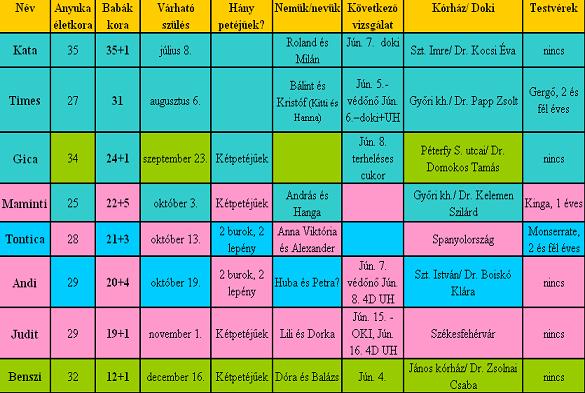

Andi

Nálunk annyira természetes, hogy nem is terveztük őket, tavaly októberben döntöttünk úgy a párommal, hogy eddig nem jött össze, (igaz csak fél évig próbálkoztunk), vissza megyek dolgozni, aztán majd később meglátjuk!!! Okt. 30-án volt menzim, nov. második hetére kaptam időpontot a dokimhoz, hogy felírassam az antibaby tablettát, de még úgy döntöttünk a párommal, hogy ez a hónap dönt, ha megjön a menzim kiváltam a bogyókat, ha nem akkor lesz egy babónk... /Nem vagyok egy templomba járós, de remélem a jó Isten tudja, hogy mit csinál(t)/ Gondolhatod alig mertem megmondani a páromnak, hogy nem egy, hanem két babónk lesz...

De most már úgy veszem észre ő jobban várja már őket, mint én!!!

Kata

Köszi szépen, megkaptam a matricát, sok-sok puszi érte, a páromnak nagyon tetszik, és persze nekem is!!! Ja és gratu a párodnak, BOLDOG SZÜLINAPOT NEKI!!!!

Benszi

Gratu a jó eredményekhez...

Én is túl vagyok a mai napon, 7-es busszal bementem a városba 3/4 8-ra már a terhesgondozóban voltam, persze a doki csak fél 9-kor jött, de gyorsan kiadta a táppénzespapírokat, aztán mentem a munkahelyemre, meglepődtek, hogy milyen szép nagy pocóm van, egy hónap alatt hatalmasat nőtt... Aztán a fél 10-es busszal haza, ja és azt hozzá kell tennem, hogy 1km-re lakunk a buszmegállótól...

Itthon a Gergőm a nyakamba, majd délután angolóra fél 4-től, fél 5-ig, azután pedig borsó fejtés...

Szóval tényleg elfáradtam ma...

Holnap védőnéni és kozmetikus...

Szex: még nálunk is zajlik igaz ritkábban, mint az elején de egyenlőre még nem okoz semmi problémát... Sőt!!!